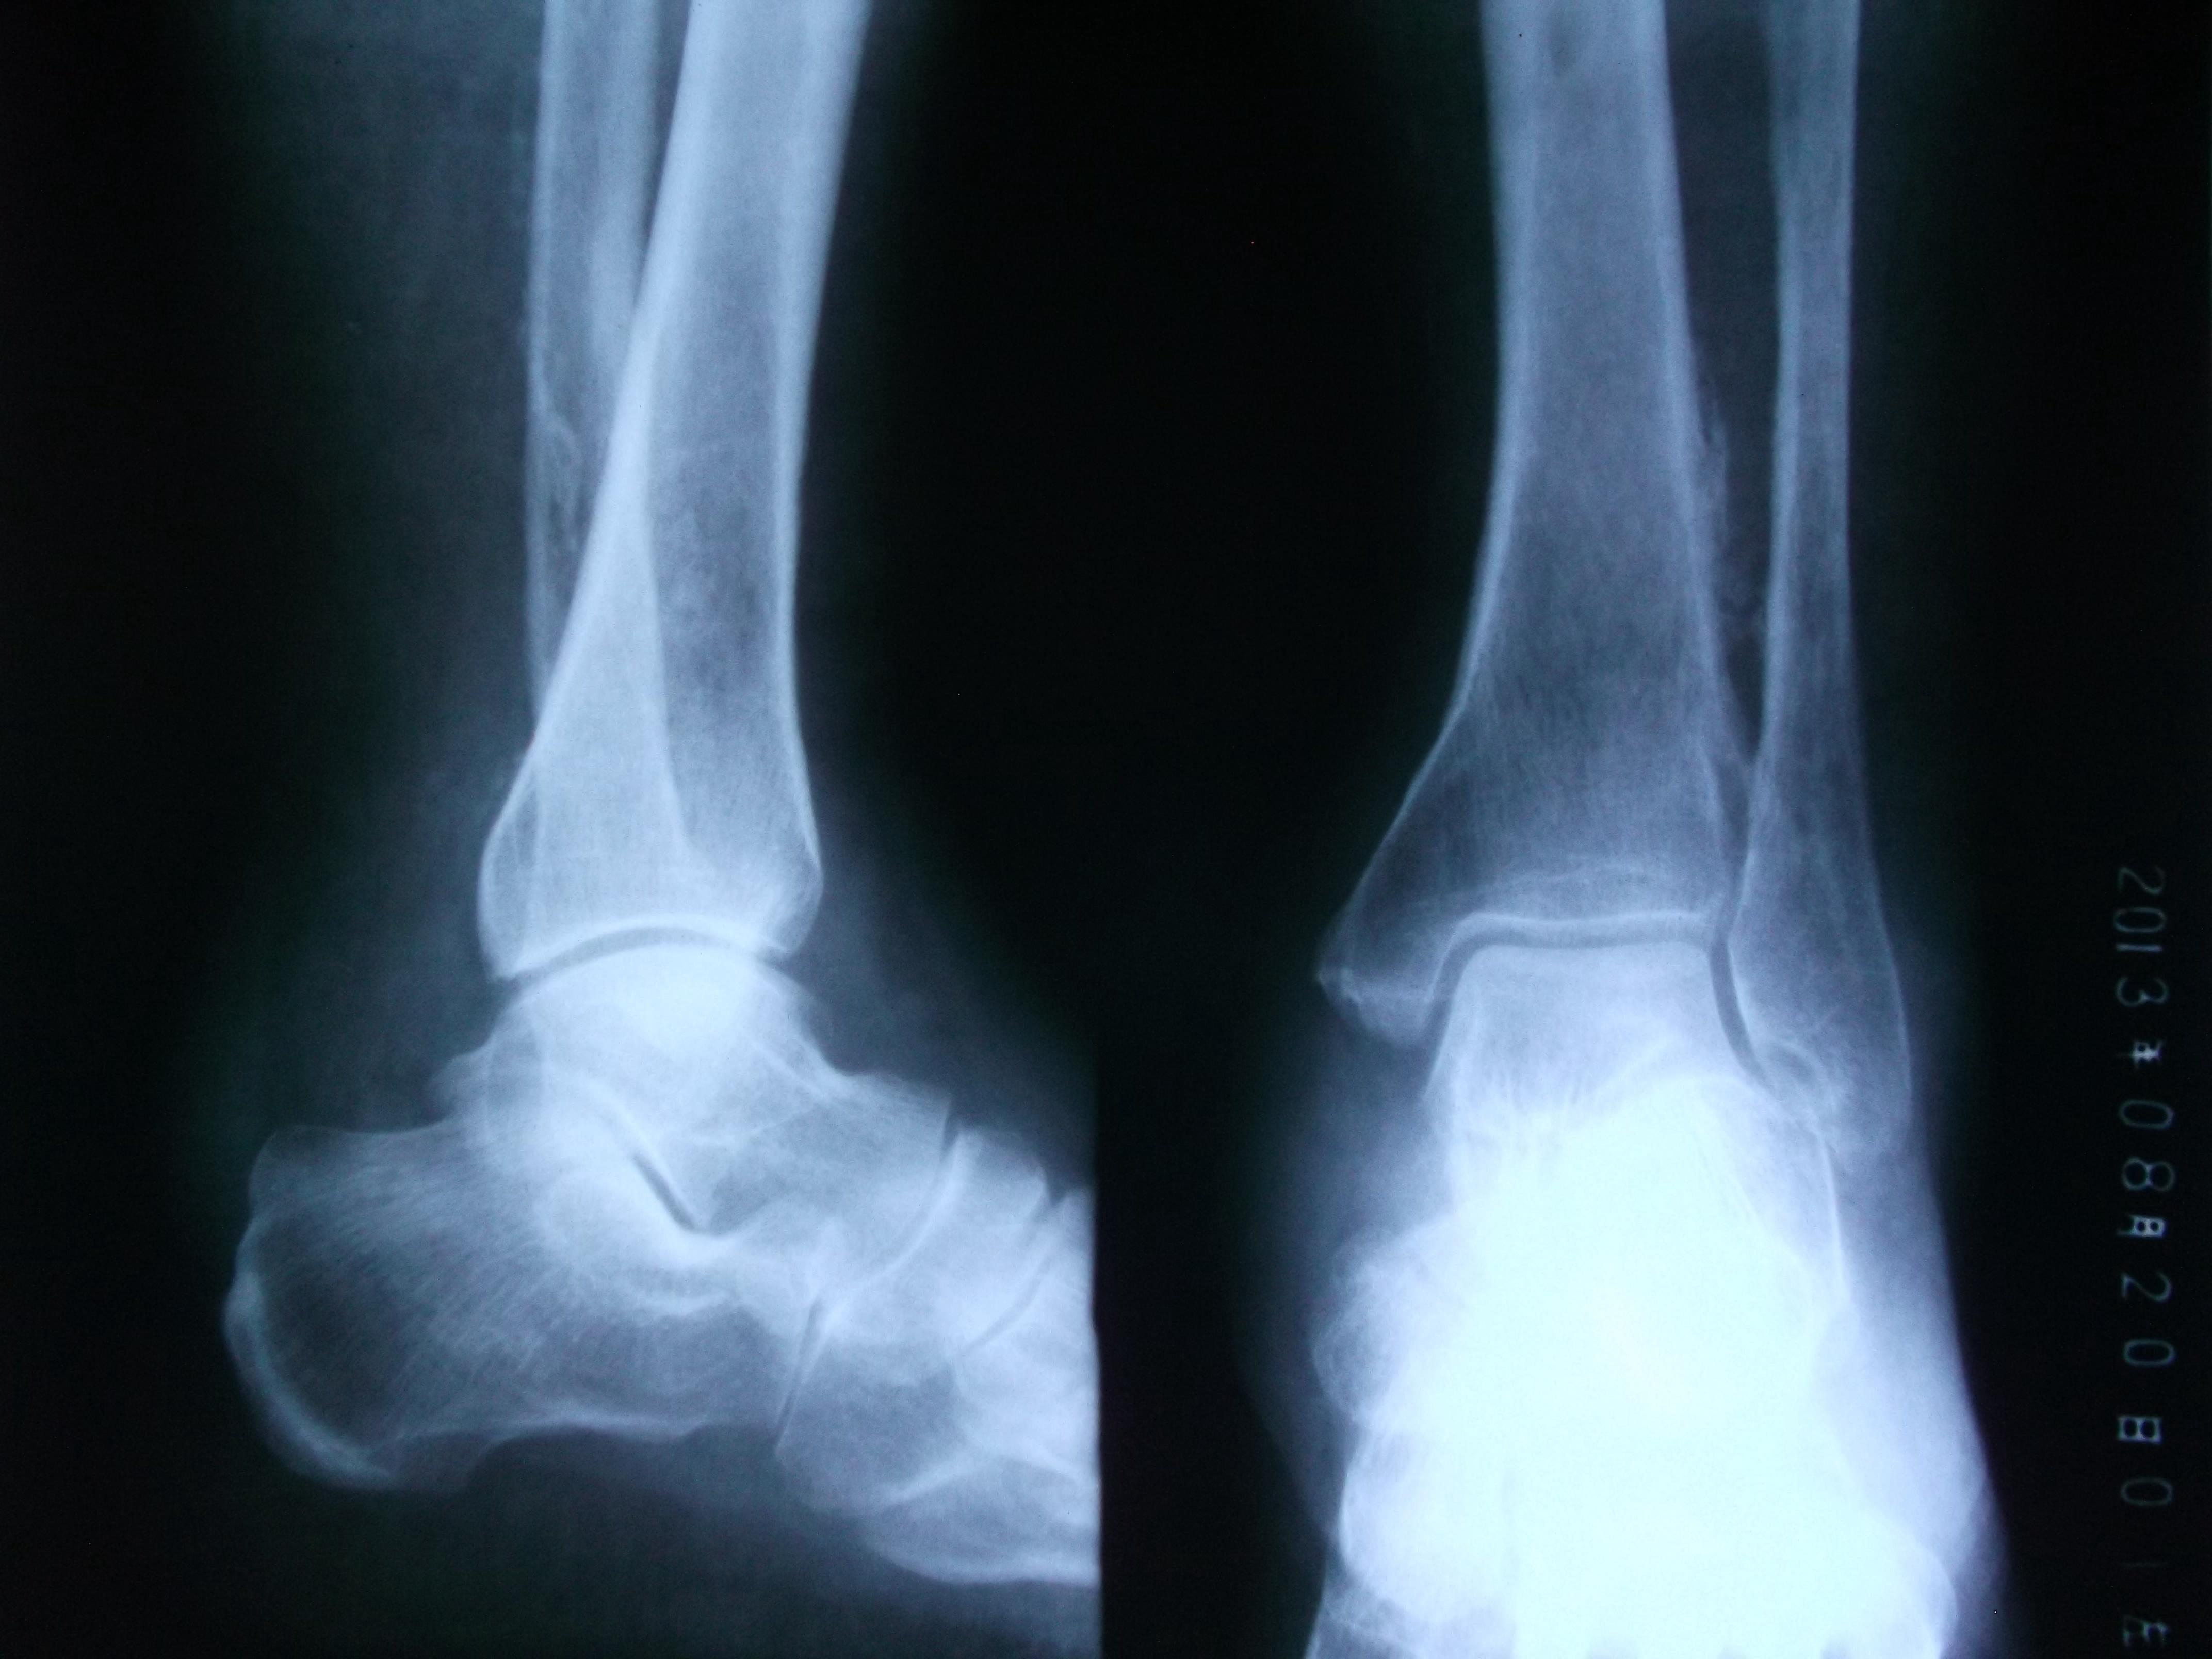

男性,56岁,左小腿静脉曲张十多年了吧,好像做过手术。现在他的整条左小腿肿胀,皮肤发黑,靠近外踝的皮肤出现溃疡。片子不太清楚,因为是基层,条件艰苦没CR。请各位前辈指点下,该患者的左胫、腓骨是什么状况,应该怎样发报告?谢谢!

患者有静脉曲张的病史,现在小腿的肌肉和皮肤都出现缺血坏死的症状;而胫腓骨X光片示胫腓骨下段向对面骨皮质增生模糊,有明显的骨膜反应;也还是考虑骨质长期缺血缺氧所致,类似肺癌所致骨皮质增生的改变。当然,骨髓炎和骨肉瘤等来源骨质本身的疾病不能完全排除。

胫腓骨下段骨皮质模糊,出现葱皮样骨膜反应,骨髓腔稍狭窄,软组织情况不清。考虑急性骨髓炎可能,为排除骨肉瘤,建议CT。